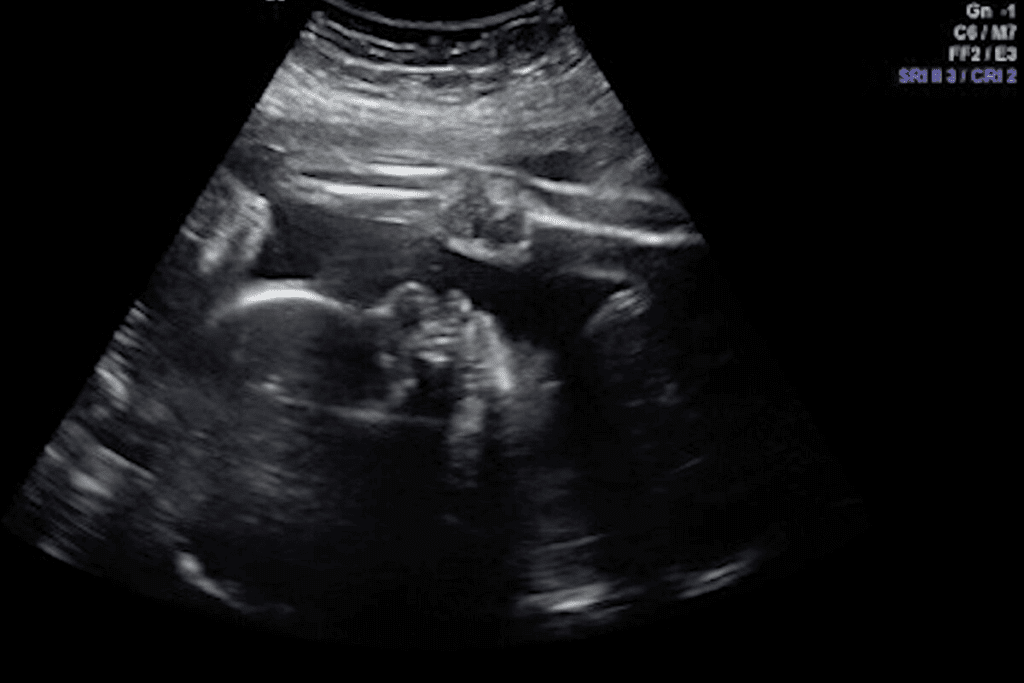

Key Structures Visible on a 7-Week Ultrasound

The 7-week ultrasound is a key moment in pregnancy. It shows important details about the embryo and its structures. At this time, several key features become visible, giving insights into the embryo’s growth and health.

Gestational Sac: Size and Appearance

The gestational sac is one of the first things seen on an ultrasound. By 7 weeks, it’s usually 18 to 24 millimeters in size. It looks like a fluid-filled area in the uterus, creating a safe space for the embryo.

Yolk Sac: Function and Normal Characteristics

The yolk sac is vital at 7 weeks. It provides nutrients to the embryo before the placenta is fully developed. A normal yolk sac looks like a small circle inside the gestational sac. Its size and presence are important for checking the embryo’s health.

Fetal Pole: What It Represents

The fetal pole is the earliest sign of the embryo. By 7 weeks, it’s about 5-10 millimeters long. Seeing the fetal pole is a big deal because it shows the embryo is growing and doing well.

Placental Development at 7 Weeks

At 7 weeks, you can see the start of placental development on an ultrasound. The placenta is a thick area around the gestational sac. It’s key for exchanging nutrients and oxygen between the mother and the embryo. Even in its early stages, the placenta is essential for the embryo’s growth.

Structure | Typical Size/Appearance at 7 Weeks | Significance |

Gestational Sac | 18-24 mm, fluid-filled | Contains the embryo, provides a safe environment |

Yolk Sac | Small, circular | Provides early nutrition to the embryo |

Fetal Pole | 5-10 mm in length | Represents the early embryo, indicates viability |

Placenta | Thickened area around the gestational sac | Facilitates nutrient and oxygen exchange |

What the Different Shades and Shapes Mean

On an ultrasound, different shades and shapes mean different things. Dark areas usually show fluids, while light areas show denser tissues. At 7 weeks, you might see the gestational sac, yolk sac, and fetal pole.

- Dark Areas: These usually show fluid-filled spaces, like the gestational sac.

- Light Areas: These show denser tissues, like the fetal pole or placenta.